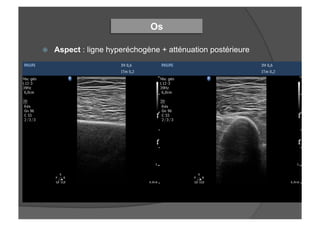

ž  Aspect : ligne hyperéchogène + atténuation postérieure

Os

ž  Aspect :ligne hyperéchogène + atténuation postérieure Os